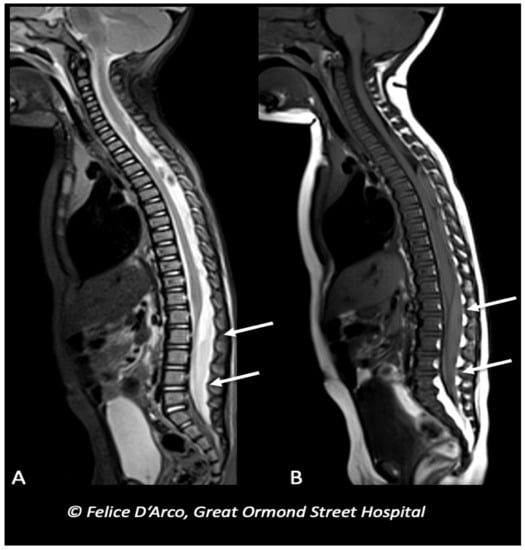

- Kemp, A.; Cowley, L.; Maguire, S. Spinal injuries in abusive head trauma: Patterns and recommendations. Pediatr. Radiol. 2014, 44, 604–612. [Google Scholar] [CrossRef] [PubMed]

- Koumellis, P.; McConachie, N.S.; Jaspan, T. Spinal subdural haematomas in children with non- Accidental head injury. Arch. Dis. Child. 2009, 94, 216–219. [Google Scholar] [CrossRef] [PubMed]

- Choudhary, A.K.; Bradford, R.K.; Dias, M.S.; Moore, G.J.; Boal, D.K.B. Spinal subdural hemorrhage in abusive head trauma: A retrospective study. Radiology 2012, 262, 216–223. [Google Scholar] [CrossRef] [PubMed]

- Choudhary, A.K.; Ishak, R.; Zacharia, T.T.; Dias, M.S. Imaging of spinal injury in abusive head trauma: A retrospective study. Pediatr. Radiol. 2014, 44, 1130–1140. [Google Scholar] [CrossRef] [PubMed]